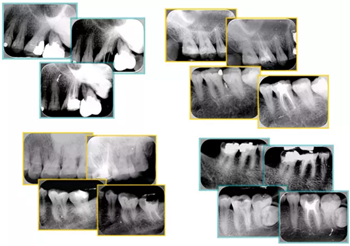

5. 不良根管充填物

常見不良根管充填物有干髓、塑化、塑化 + 根充和不良根充。

( 1 )干髓。

干髓治療時,開髓后髓腔里注入甲醛甲酚 FC 灌髓,三聚甲醛固定,髓室底放置三聚甲醛緩慢釋放,進(jìn)行根管無害化處理。髓腔緩慢壞死,機(jī)體代償出現(xiàn)根管鈣化。如果患者在封閉腔出現(xiàn)出現(xiàn)病變,由于髓腔鈣化,根管堵塞嚴(yán)重,檢查治療比較困難。

上圖為干髓治療后牙齒,齲齒疏通后進(jìn)行根管充填。

( 2 )塑化

傳統(tǒng)的治療思維:塑化治療后患者需將塑化液清理干凈,達(dá)到徹底根管治療目的。

目前的治療思維:以前塑化治療效果好時不必清理干凈塑化液。對于根尖沒有病變的患者,可借助溶解劑建立通路;根尖存在病變的患者往往是塑化治療不理想患者,需要徹底打通通路。

( 3 )塑化 + 根充。

如圖為塑化加根充處理后牙齒 X 線片。

( 4 )不良根充。

不良填充與操作有關(guān),采用輔助放大設(shè)備可有效預(yù)防不良填充